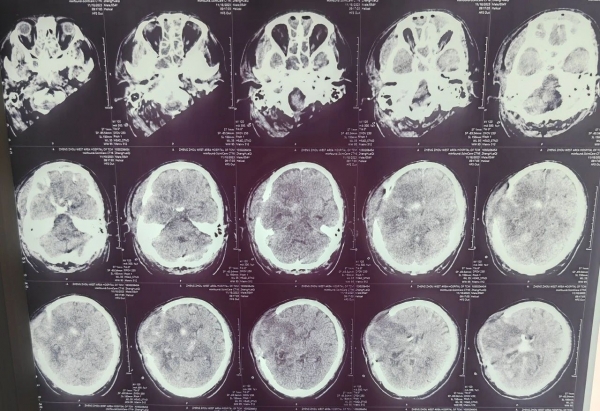

(術(shù)后20天)

張大叔轉(zhuǎn)危為安

目前有呼叫意識(shí)

肢體肌力逐漸恢復(fù)